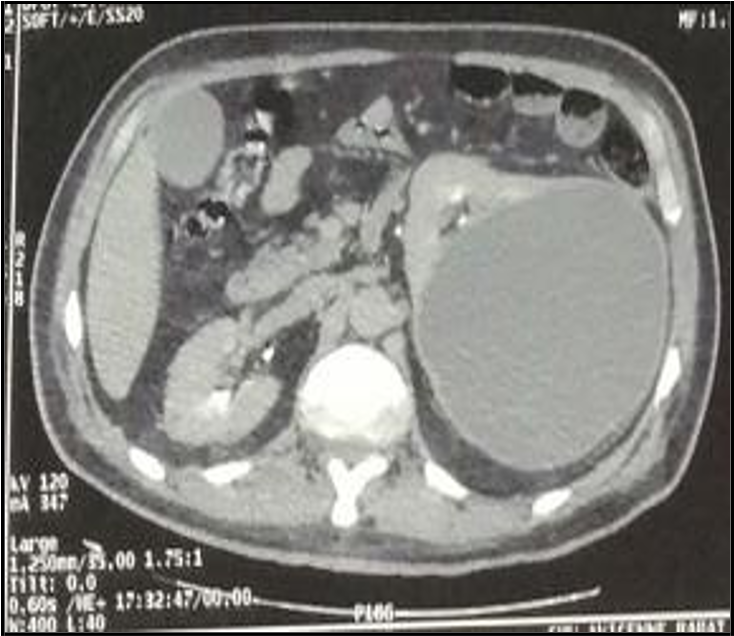

Despite 48 hours of antibiotic treatment, there was no clinical or biological improvement. A contrast-enhanced abdominal and pelvic CT scan (excretory phase) confirmed the findings without providing further diagnostic clarity (Figures 1 and 2).

Figure 1: Coronal section from an abdominal CT scan in the arterial phase showing a 17 cm renal cyst with contrast-enhancing wall and hypodense content.

Figure 2: Coronal section from a delayed-phase abdominal CT scan showing a 17 cm renal cyst with contrast-enhancing wall and hypodense content. No communication was observed between the cyst and the pelvicalyceal system.